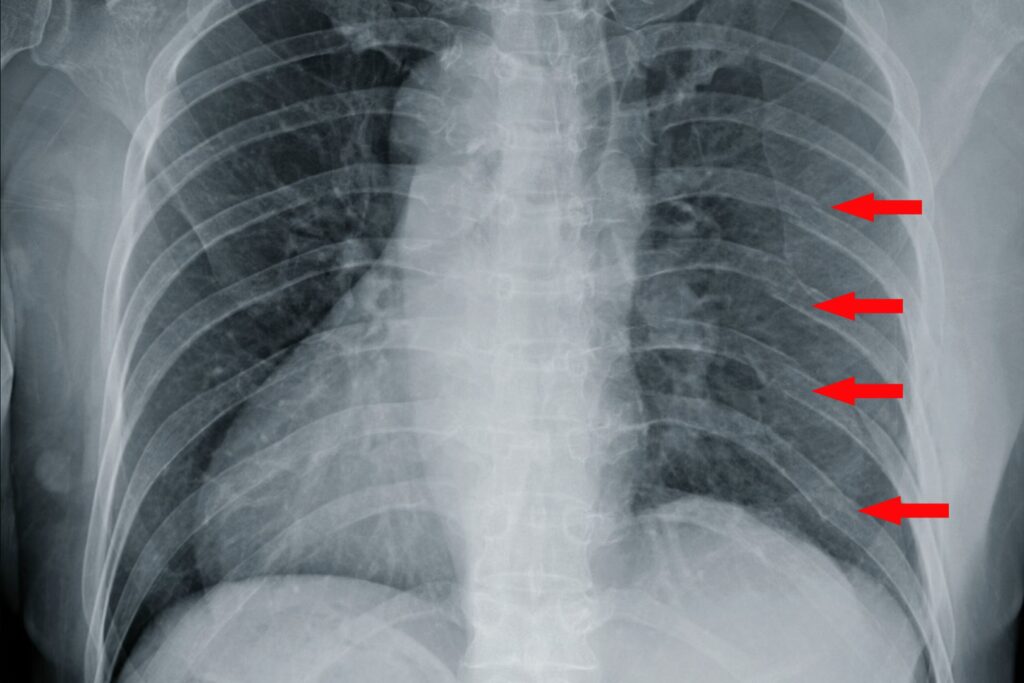

En læge vil typisk kunne stille en formodet diagnose baseret på dine symptomer og en fysisk undersøgelse. For at bekræfte bruddet og udelukke komplikationer kan billeddiagnostik være nødvendig. Et røntgenbillede kan ofte vise bruddet, men det er ikke ualmindeligt, at især revner ikke er synlige. I op til 50% af tilfældene kan et røntgenbillede ikke vise et eksisterende brud. Derfor fravælges det nogle gange, da det sjældent ændrer behandlingsplanen for et ukompliceret brud. Ved mistanke om flere brud, skader på indre organer som lungerne (f.eks. en punkteret lunge/pneumothorax) eller ved alvorlige traumer, kan en CT-scanning give et meget mere detaljeret billede.